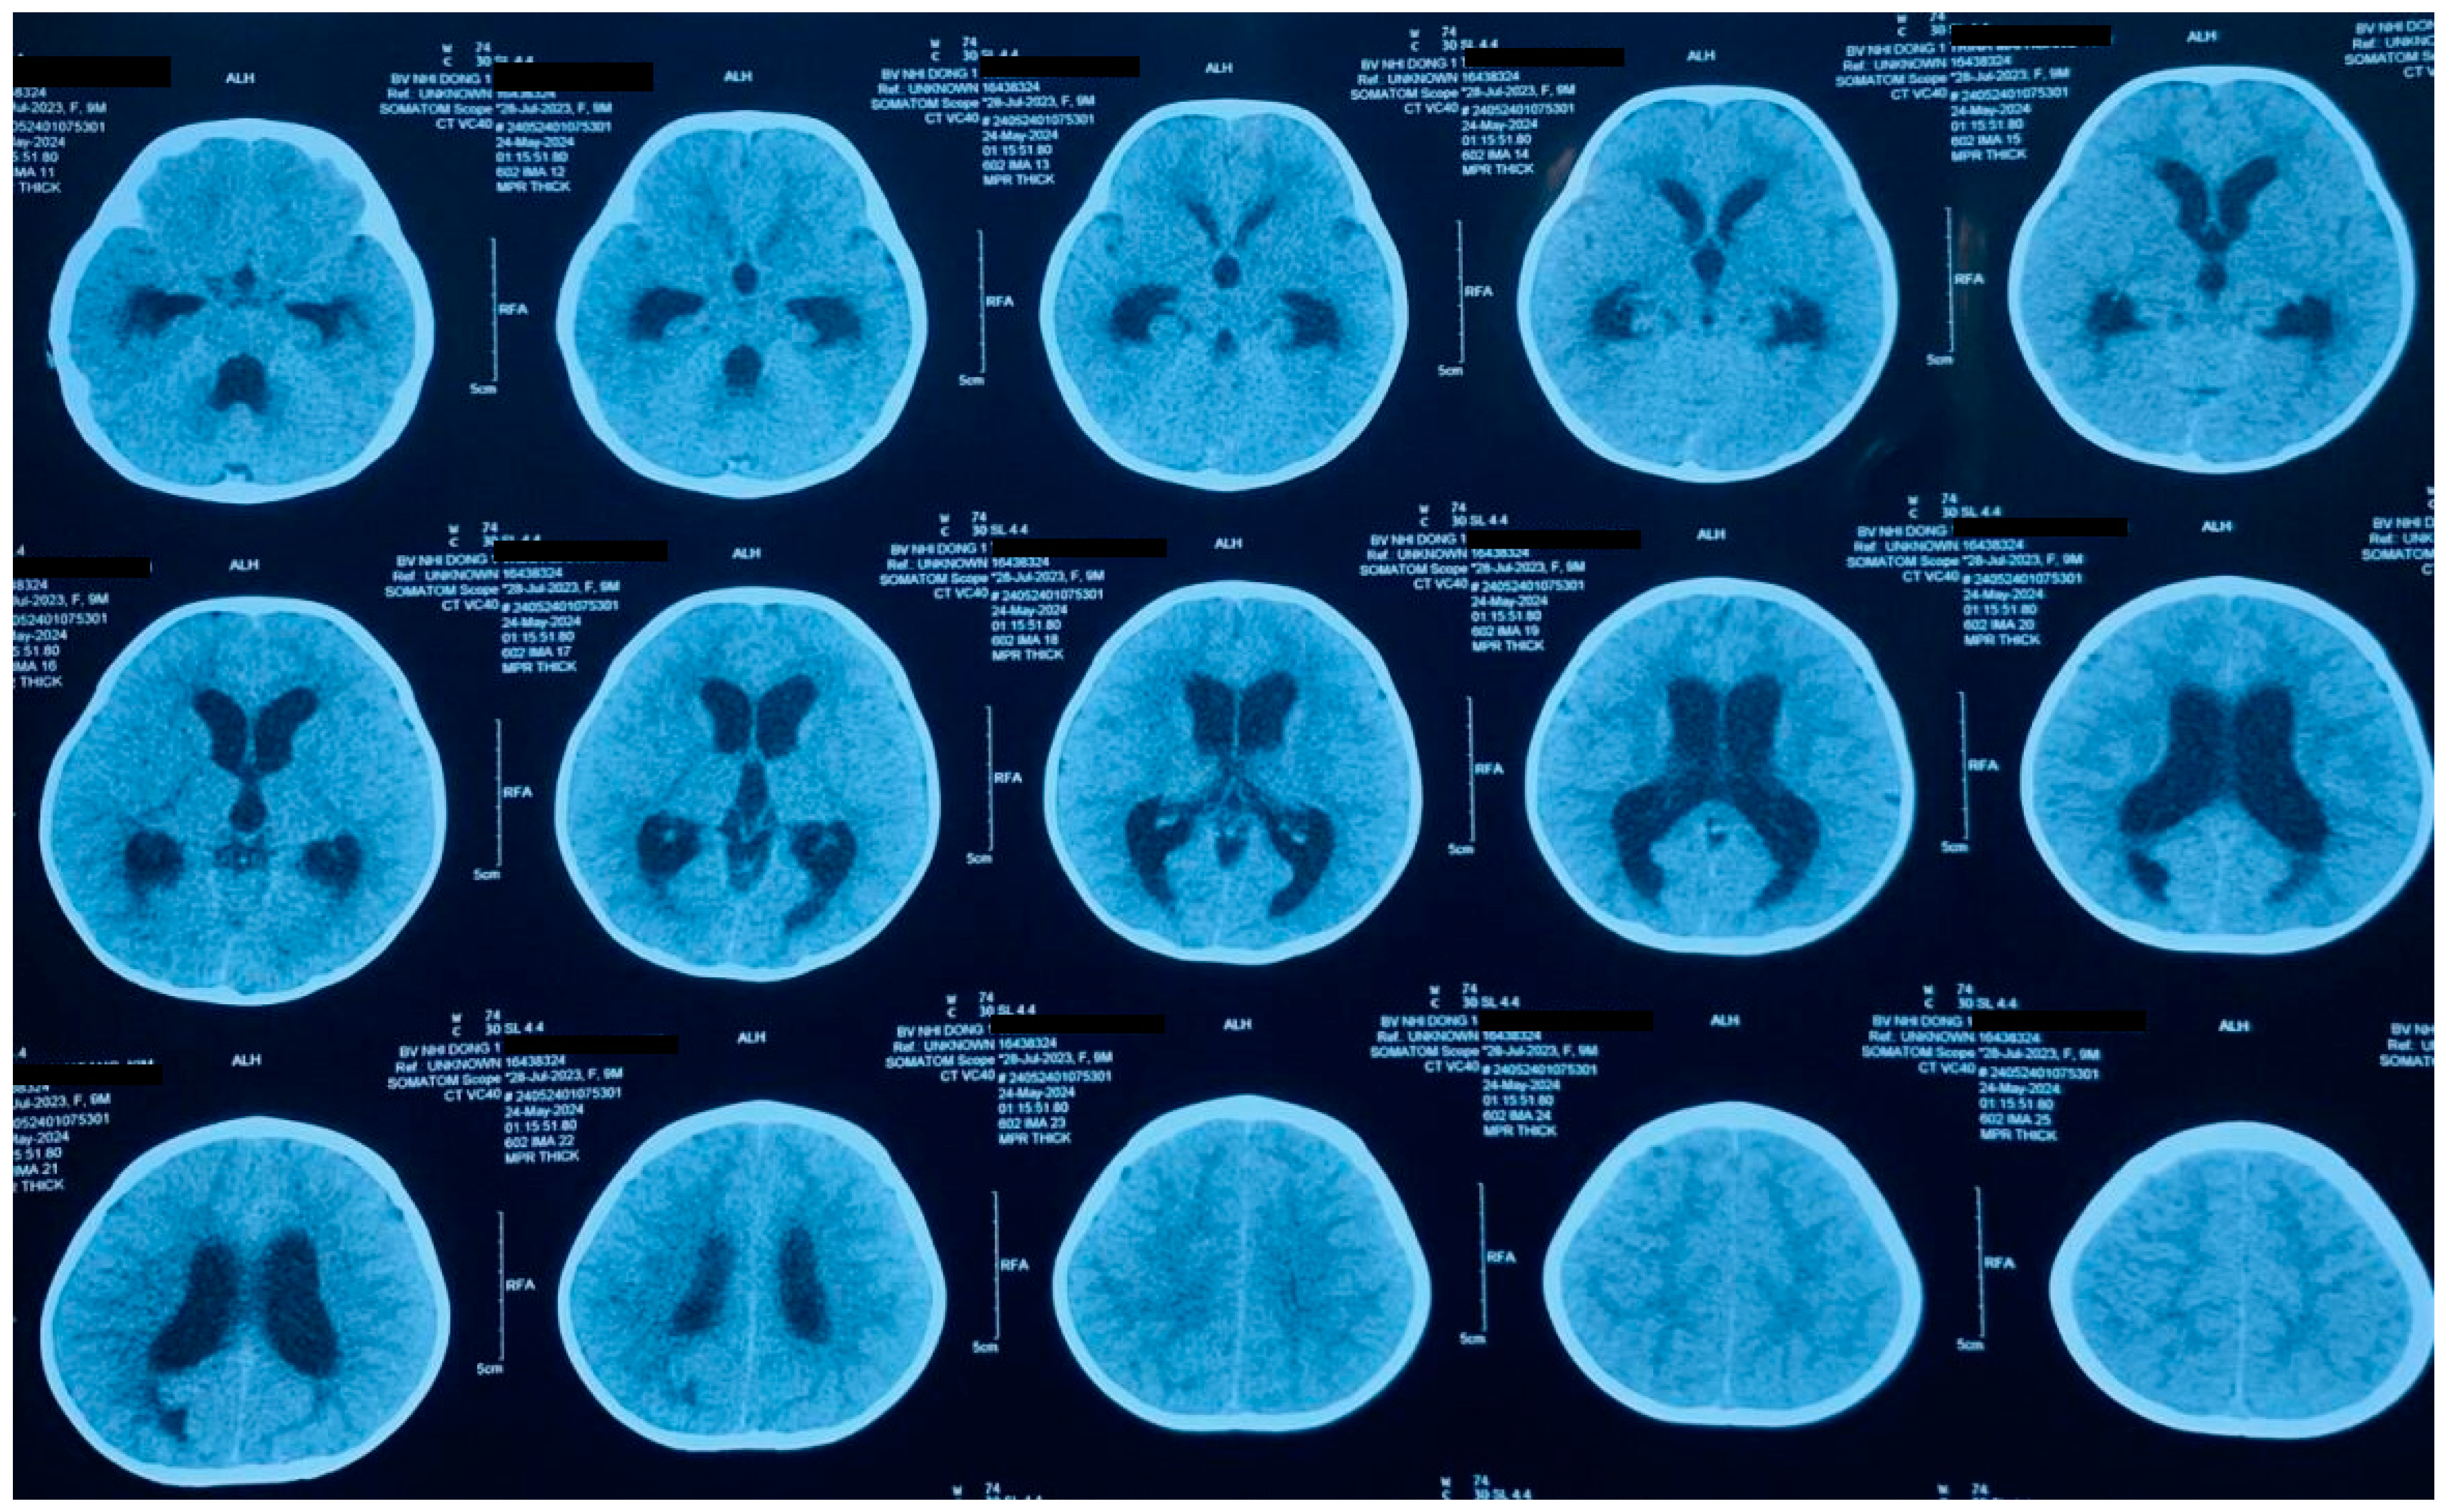

2. Case Presentation